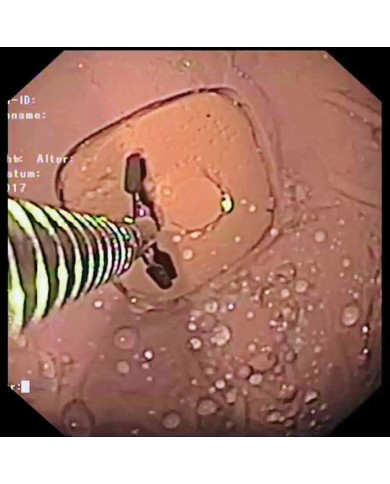

In campo medico, la colangio-pancreatografia endoscopica retrograda è laprocedura endoscopica che permette di visualizzare le vie bilari e pancreatiche.

La tecnica consiste nella cannulazone della papilla di Vater e nell'iniezione di un mezzo di contrasto, che viene poi preso a scansione con l'utilizzo di una tecnica radiologica.

La tecnica viene effettuata per mezzo di strumenti sspecfici, quali endoscopi appositamente costruiti, detti duodenoscopi, la cui peculiarità è la visione laterale del lume intestinale.